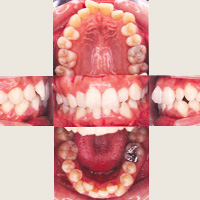

お話の過程で必要であれば、口腔内写真、顔貌写真などを撮らせていただきます。

歯の本数や位置、上下顎骨の位置などを調べるために、レントゲン、セファロ、診断用模型を製作するための歯型、かみ合わせの型を採ります。